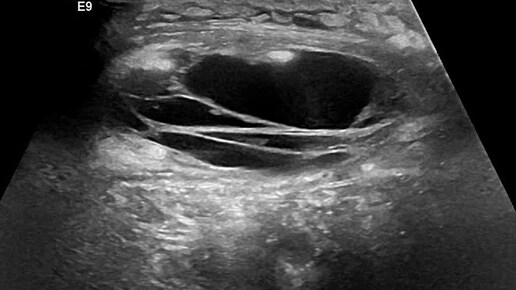

Видео к статье "Разрыв икроножной мышцы".https://dzen.ru/a/Z8AwLJ00NlZOFhsx

Ультразвуковые находки от врача УЗД Зорина Я.П.